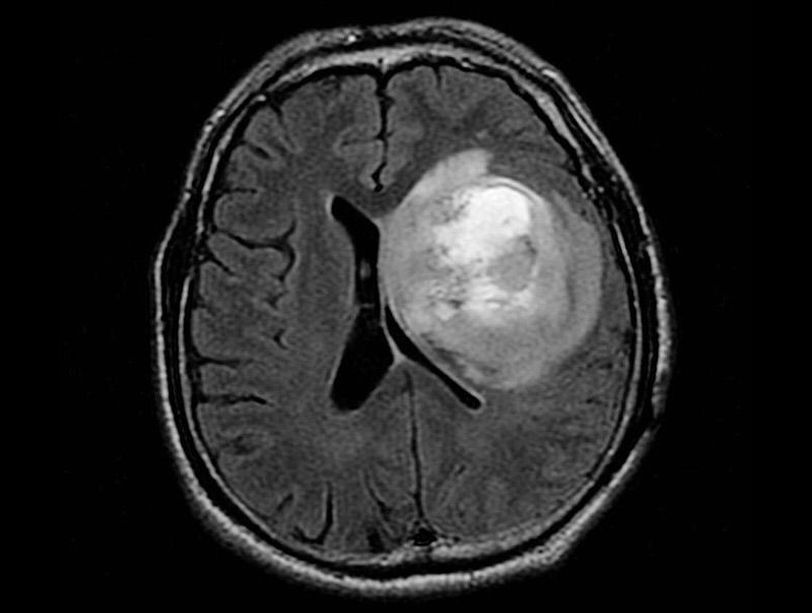

Glioblastomas are generally found in the cerebral hemispheres of the brain, but can be found anywhere in the brain or spinal cord. Glioblastomas usually contain a mix of cell types. It is not unusual for these tumors to contain cystic mineral, calcium deposits, blood vessels, or a mixed grade of cells. Glioblastomas are usually highly malignant—a large number of tumor cells are reproducing at any given time, and they are nourished by an ample blood supply. Dead cells may also be seen, especially toward the center of the tumor. Because these tumors come from normal brain cells, it is easy for them to invade and live within normal brain tissue. However, glioblastoma rarely spreads elsewhere in the body.